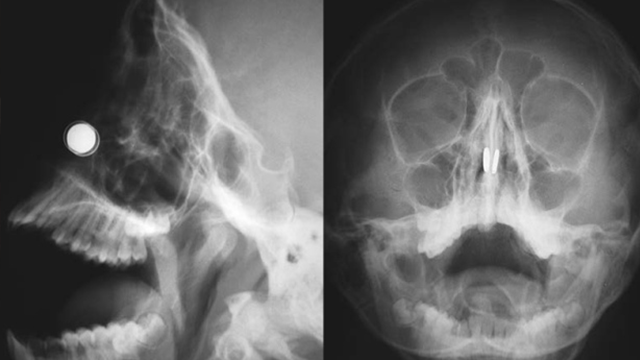

Konuyla ilgili açıklamalarda bulunan Doç. Dr. Kadir Çağdaş Kazıkdaş, en güçlü mıknatıslardan olan neodyum mıknatıslarının buruna girer girmez çocuğun burun direği etrafında birbirine yapıştığını açıkladı. Çocuğun mıknatısları burnuna soktuktan yaklaşık altı saat sonra dayanılmaz bir ağrı, burun kanaması ve burun içinde kabuklanma şikayetleri ile hastanenin acil servisine getirildiğini ifade eden Doç. Dr. Kazıkdaş, yapılan ilk müdahalede mıknatısların halen çocuğun burnunda olup olmadığının kesin olarak anlaşılamadığını, burun içerisinde de kanamaya bağlı çok fazla kabuklanma olduğunu, bu arada çocuğun duyduğu ağrı ve korku nedeniyle doktorların müdahale girişimlerini de engellediğini söyledi. Doç. Dr. Kazıkdaş daha sonra hastanın Kulak, Burun Boğaz Polikliniği’ne sevk edilerek, yüz röntgeninin çekildiğini, böylece burun içerisinde birbirine kenetlenmiş olan mıknatısların tespit edilebildiğini söyledi.

Geleneksel cerrahi aletlerle mıknatısları çıkarmayı denediklerini ama bu şekilde sonuç alamadıklarını ifade eden Doç. Dr. Kadir Çağdaş Kazıkdaş, son olarak burun içinde kenetlenmiş olan mıknatısları kaldırıp çıkarmak için burun dışından sıradan mıknatıslar kullanmayı düşündüklerini ifade ederek şöyle devam etti; “Bu yöntem ile sol taraftaki mıknatısı kolaylıkla çıkarmayı başardık. Ardından ikinci mıknatısı çıkarmak da saniyeler sürdü. Çocuğun burun kıkırdağında oluşan hasarlı bölgeye ve travmatize olan dokulara yapay yama uygulandı. İlerleyen dönemdeki iyileşmeyi desteklemesi için silikon burun ateli de takıldı. Atel operasyon sonrasında on gün boyunca hastanın burnunda takılı kaldı.”